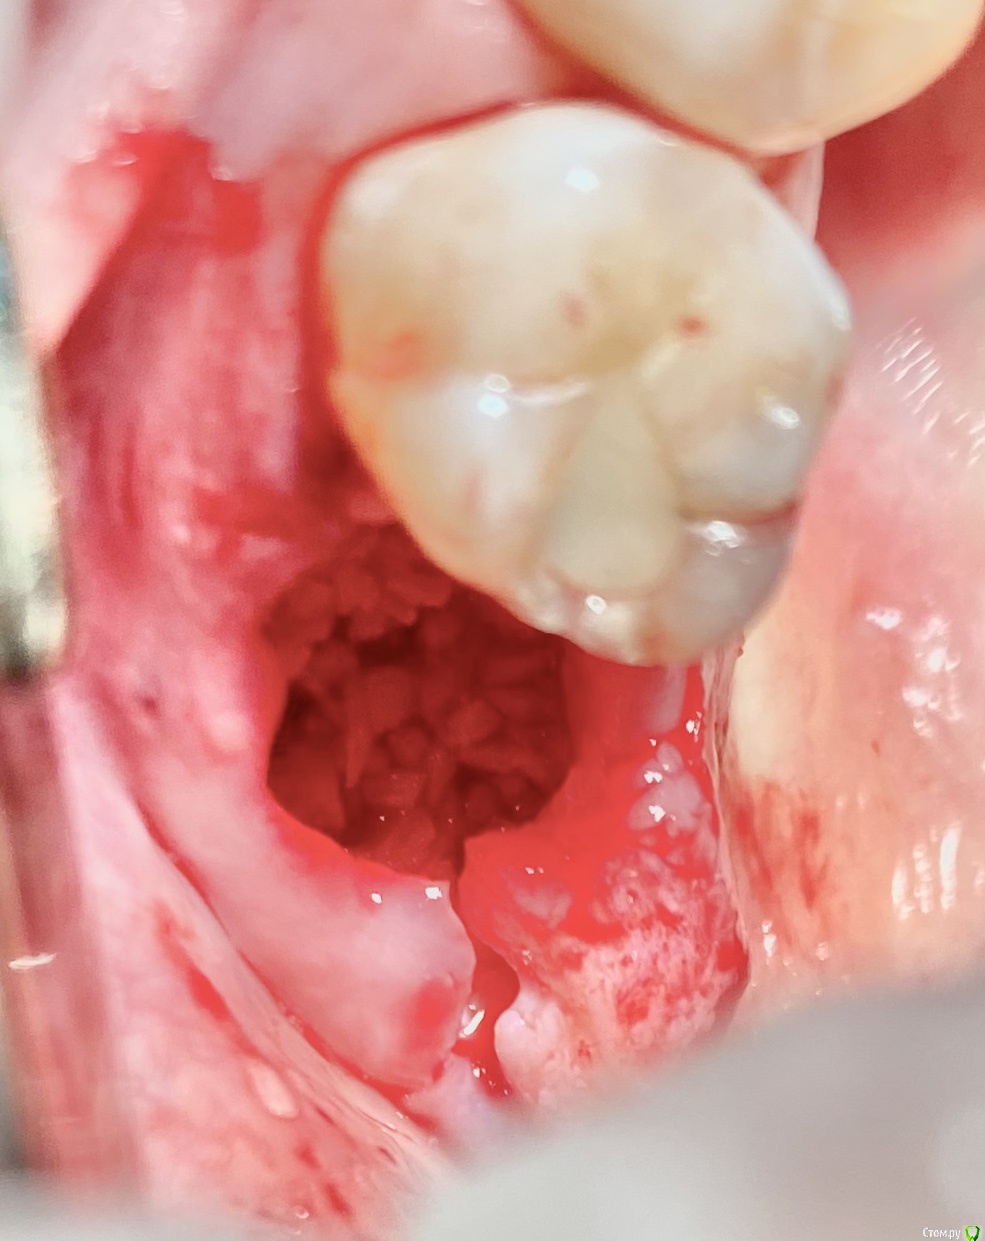

колесников Опубликовано 11 сентября, 2020 Поделиться Опубликовано 11 сентября, 2020 Перемещение бугра для закрытия лунки. Вестибулярно прикрепленную не смещаем. Вестибулярно компактной пластинки нет 9 Ссылка на комментарий

колесников Опубликовано 9 сентября, 2020 Поделиться Опубликовано 9 сентября, 2020 Т.е. на месте кривой это подслизистое отслоение, а где овал - это бугор, который нужно ротировать? овал-это бугор который мы видим и зачастую используем. Кривая-это бугор который можно забрать под слизистой. Конечно чем дальше к периферии ,тем его качество падает ,но он есть. Делаете поверхностный разрез ретромолярно,расщепляете,выделяете лоскут -заплатку,обрезаете её вестибулярно,дистально. Небно отступаете от края мм на 5 и проводите разрез до дистального края 7ки. Отделяете от основания. У вас получается заплатка на ножке. Перекидываете ее на гребень и вносите под вестибулярный край лоскута лунки,фиксируя матрасным швом. Далее придавливаете ножку перекидными швами небно-вестибулярно (ножек не прошиваем,только прижимаем). 3 Ссылка на комментарий